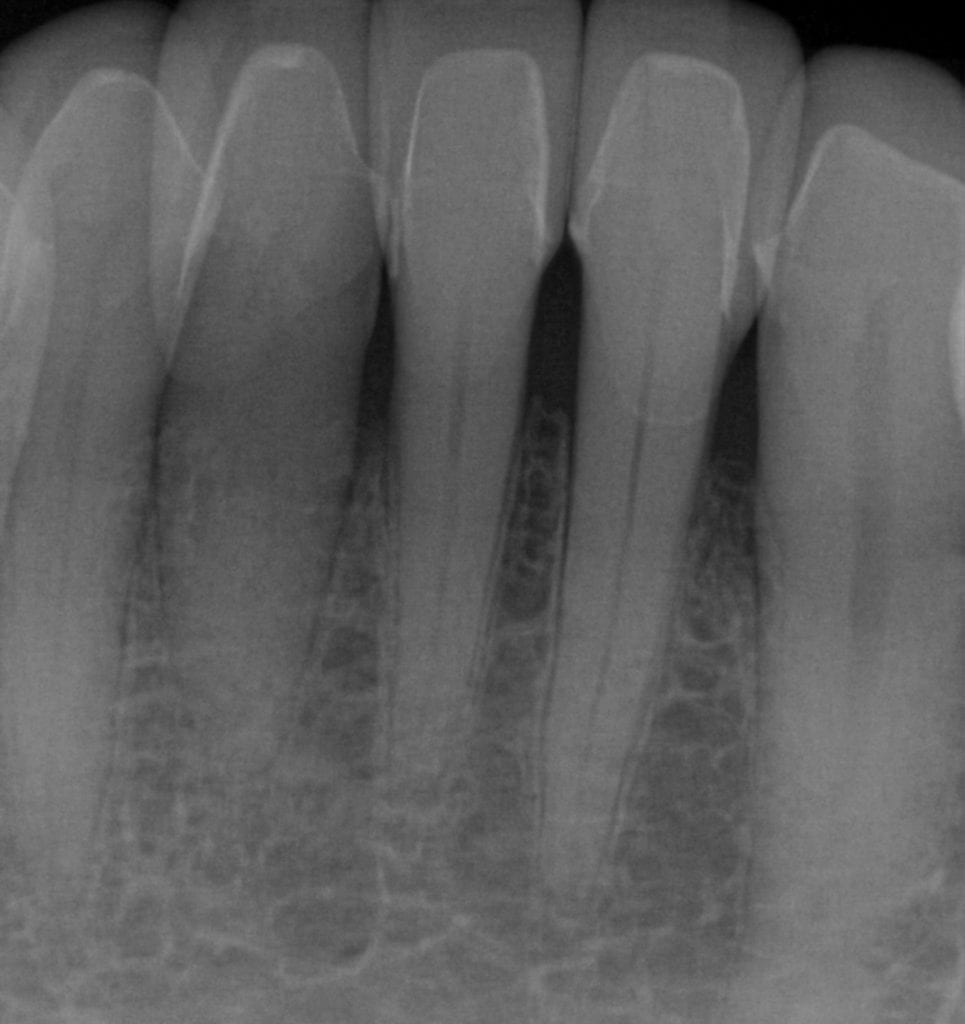

ONE WEEK POST-OP RADIOGRAPHS / CEMENT CHECK